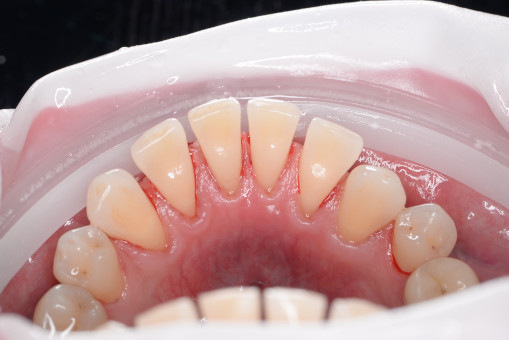

А прежде, чем вы посмотрите фотографии «до» и «после» лечения слизистой оболочки полости рта, проведенных в нашей клинике, хочу поблагодарить большое количество наших пациентов, которые поверили, прониклись нашей концепцией, и мы вместе, именно вместе победили болезни десны, гингивит и пародонтит!

До/после лечения